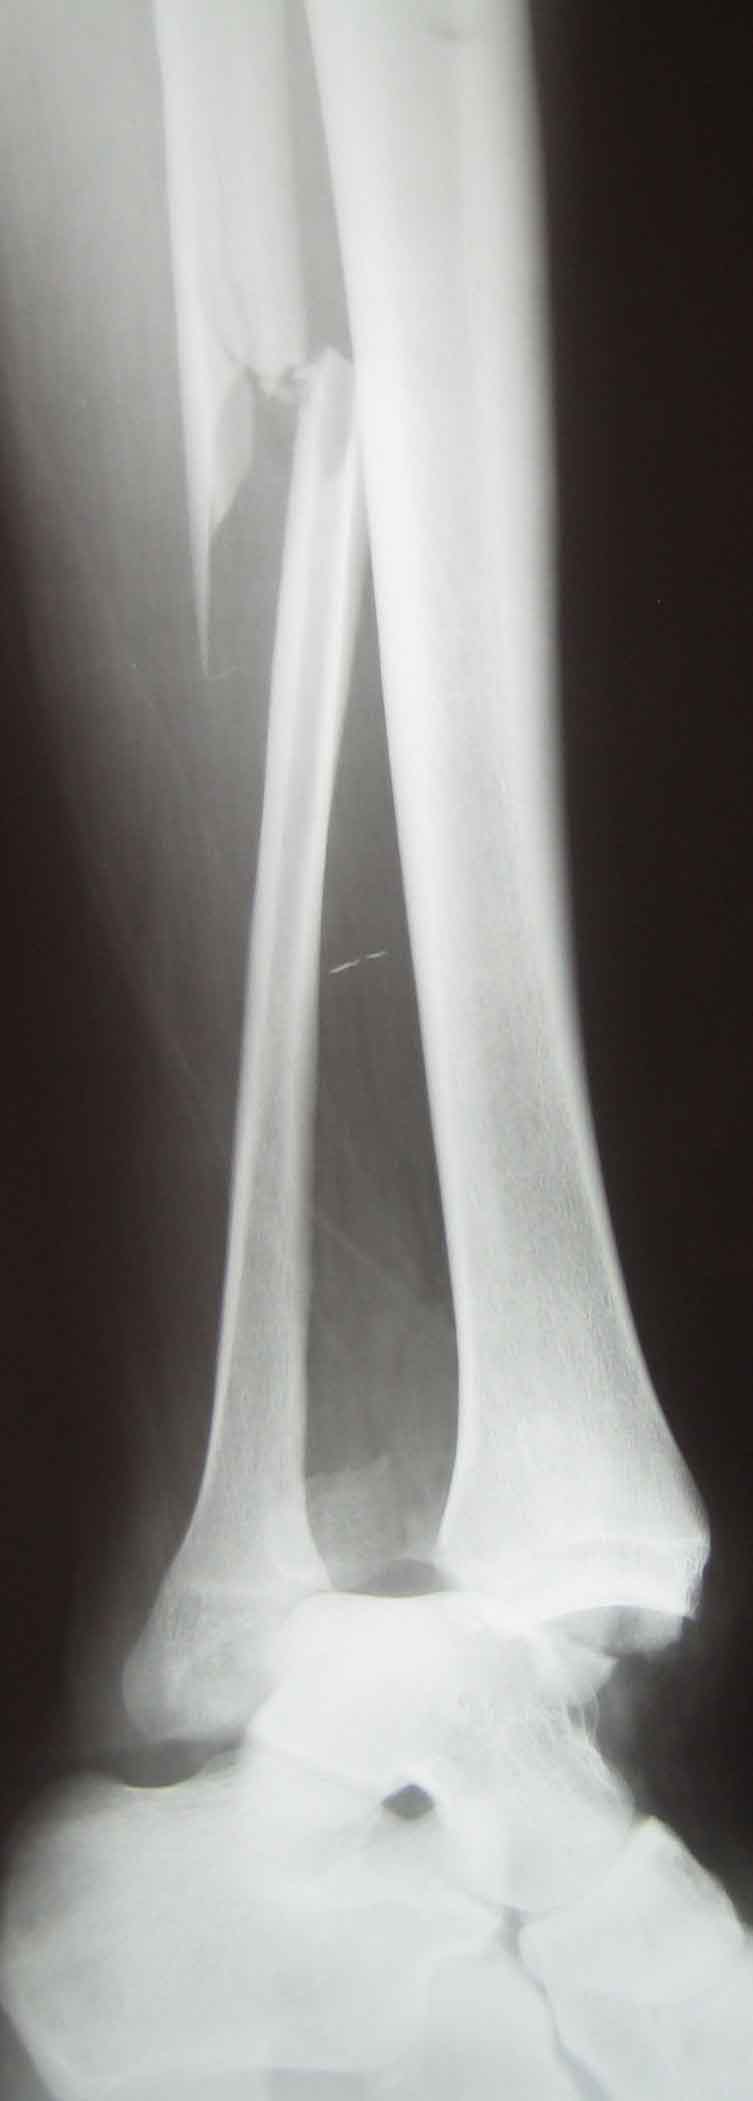

Д-з: закрытый переломо-вывих правого голеностопного сустава, перелом

Травма тяжелая, ожидаем большой отек вскоре. Что сделать - сильно зависит от возможностей учреждения, и при поступлении. Можно и закрыто вправить, наложив гипс, или положить на вытяжение, а загипсовать по спадении отека. Можно вправить и фиксировать аппаратом временно или окончательно, а можно вправить и ввести под ЭОП несколько винтов через проколы.

Классическая надсиндесмозная травма, соответственно классическое лечение: цапкой перкутанно за латеральную лодыжку тракция , внутренняя ротация, вставляем в вырезку малоберцовку, сжимаем, вводим позиционный винт через три кортикала , минидоступ на внутреннюю лодыжку, репозиция фиксация губчатым винтом. Рентген-контроль.Задний край малого размера, встанет сам на место. Оперировать можно сразу в первые 5 часов или через 5-6 дней по спадению отека, (держать на ДСВ). Пластину при желании можно простую треть трубки через два разреза на 4 винта, по малоинвазивной методике, а можно без пластины, перелом высоко, мышщ много.

Надсиндесмозная травма с разрывом не только межберцового синдесмоза, но и межкостной мембраны на большом протяжении. По-этому ( кожа и ex-fix, повторяться не буду, фиксация малоберцовой открыто или минидоступом-по желанию хирурга), но я бы провел ДВА позиционных винта (кортикальных 3,5 мм) и через четыре кортикала.

Povrezdenije tipa "Maisonneuve" . Otsen plohoje . Kak vise kollega pisal povrezden ne tolko sindesmos no i mezkostnaja membrana . V dobavok ko vsemu povrezdenija v oblasti golenostopa vsegda VNUTRISUSTAVNIJE ! Po etomu vosstanovlenije anatomii vazno . I zakritije manipulatsii s malobertsovoi v etom slutsaje , na moi vzgljad, ne dopustimi .

Определяющим в выборе метода первичной фиксации явилось то, что с момента травмы прошло менее часа. Анестезия - местная. Перелом из категории "трудновправимых, но неудержимых", поэтому скелетное вытяжение было бы неэффективным. Аппарат Илизарова стоял "под парами" на случай усугубления ситуации.

К исходу месяца обсуждали вариант перехода на фиксацию синдесмоза и лодыжки винтами, но пациента это не вдохновило. В гипсе - 2,5 мес., потом сразу поехал в отпуск, поэтому справа нога такая загорелая, хотя и немного отечная. Сейчас 10 мес., всё нормально. По осени сустав немного реагировал на смену погоды.